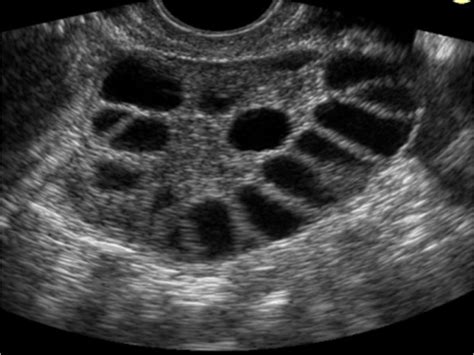

Az ovuláció kiszámításához többféle módszer is rendelkezésre áll, mint például az ovulációs tesztek, a naptármódszer, a bazális hőmérséklet mérése és a méhnyaknyák megfigyelése. A follikulometria, azaz a tüszőérés ultrahangos nyomon követése, egy megbízható módszer a peteérés legvalószínűbb időpontjának megállapítására.